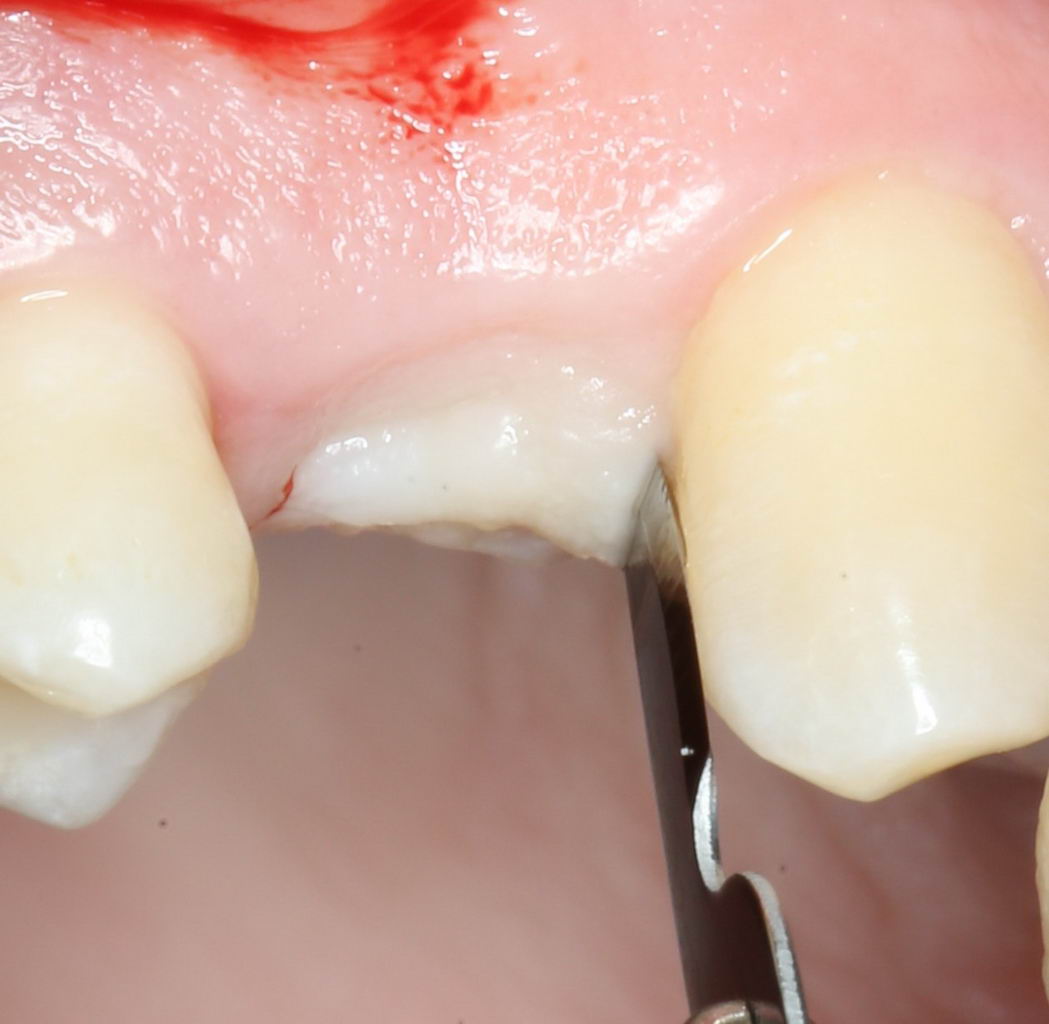

Разрез и скелетирование альвеолярного гребня.

Разрез и скелетирование делаются, исходя из двух взаимоисключающих нюансов: с одной стороны, разрез должен быть минимально травматичным, с другой — обеспечивать хороший обзор:

Мы немного смещаем разрез в сторону нёба для того, чтобы потом нормально сформировать десну. Это видно на правой фотографии выше.